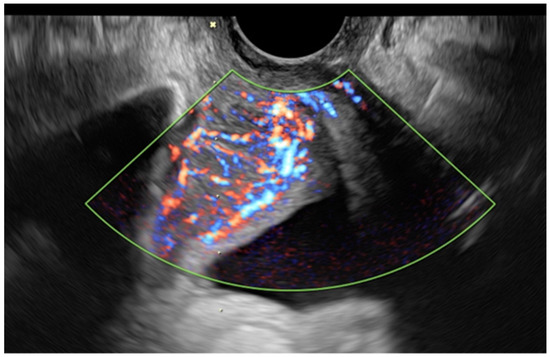

| Color score (N, %) | |

| 2 | 10 (23.8%) |

| 3 | 29 (69%) |

| 4 | 3 (7.1%) |

| Site of access (N, %) | |

| Transvaginal | 31 (73.8%) |

| Transabdominal | 11 (26.2%) |